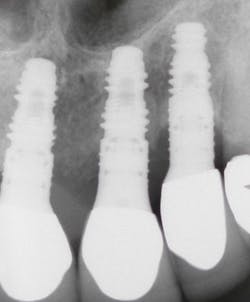

A patient had four quadrants of scaling and root planing in the office of her general dentist. Subsequently, three maxillary anterior implants were placed. The patient was scheduled every six months for periodontal maintenance visits. Radiographs taken prior to the scaling and root planing (figure 4) revealed moderate periodontitis with slight vertical bone loss involving the mandibular left first molar. A deep vertical osseous defect on the distal of the second molar was present.